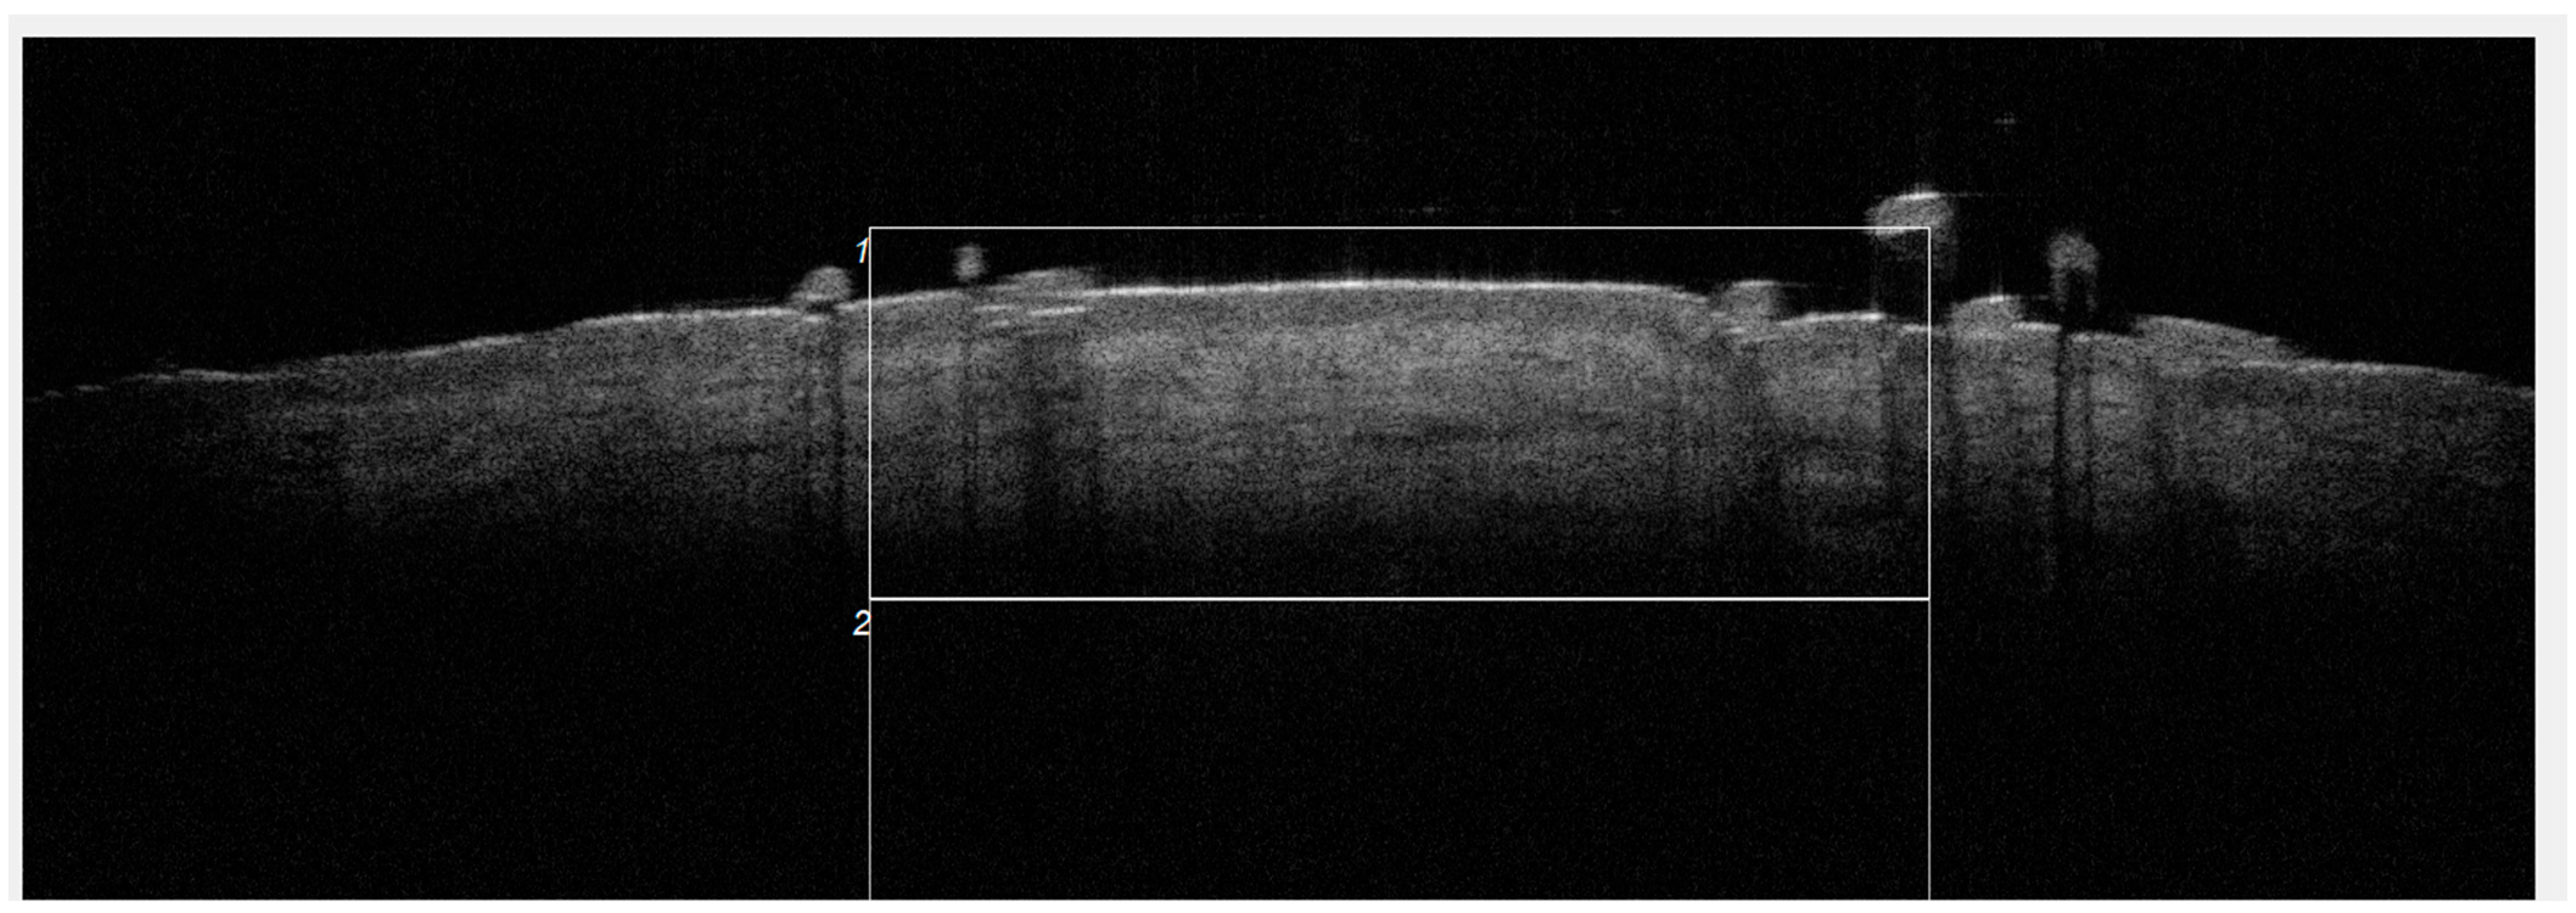

Dynamic OCT Data Analysis

3.3. Attenuation Changes

2. Materials and Methods

2.2. Treatment Protocol